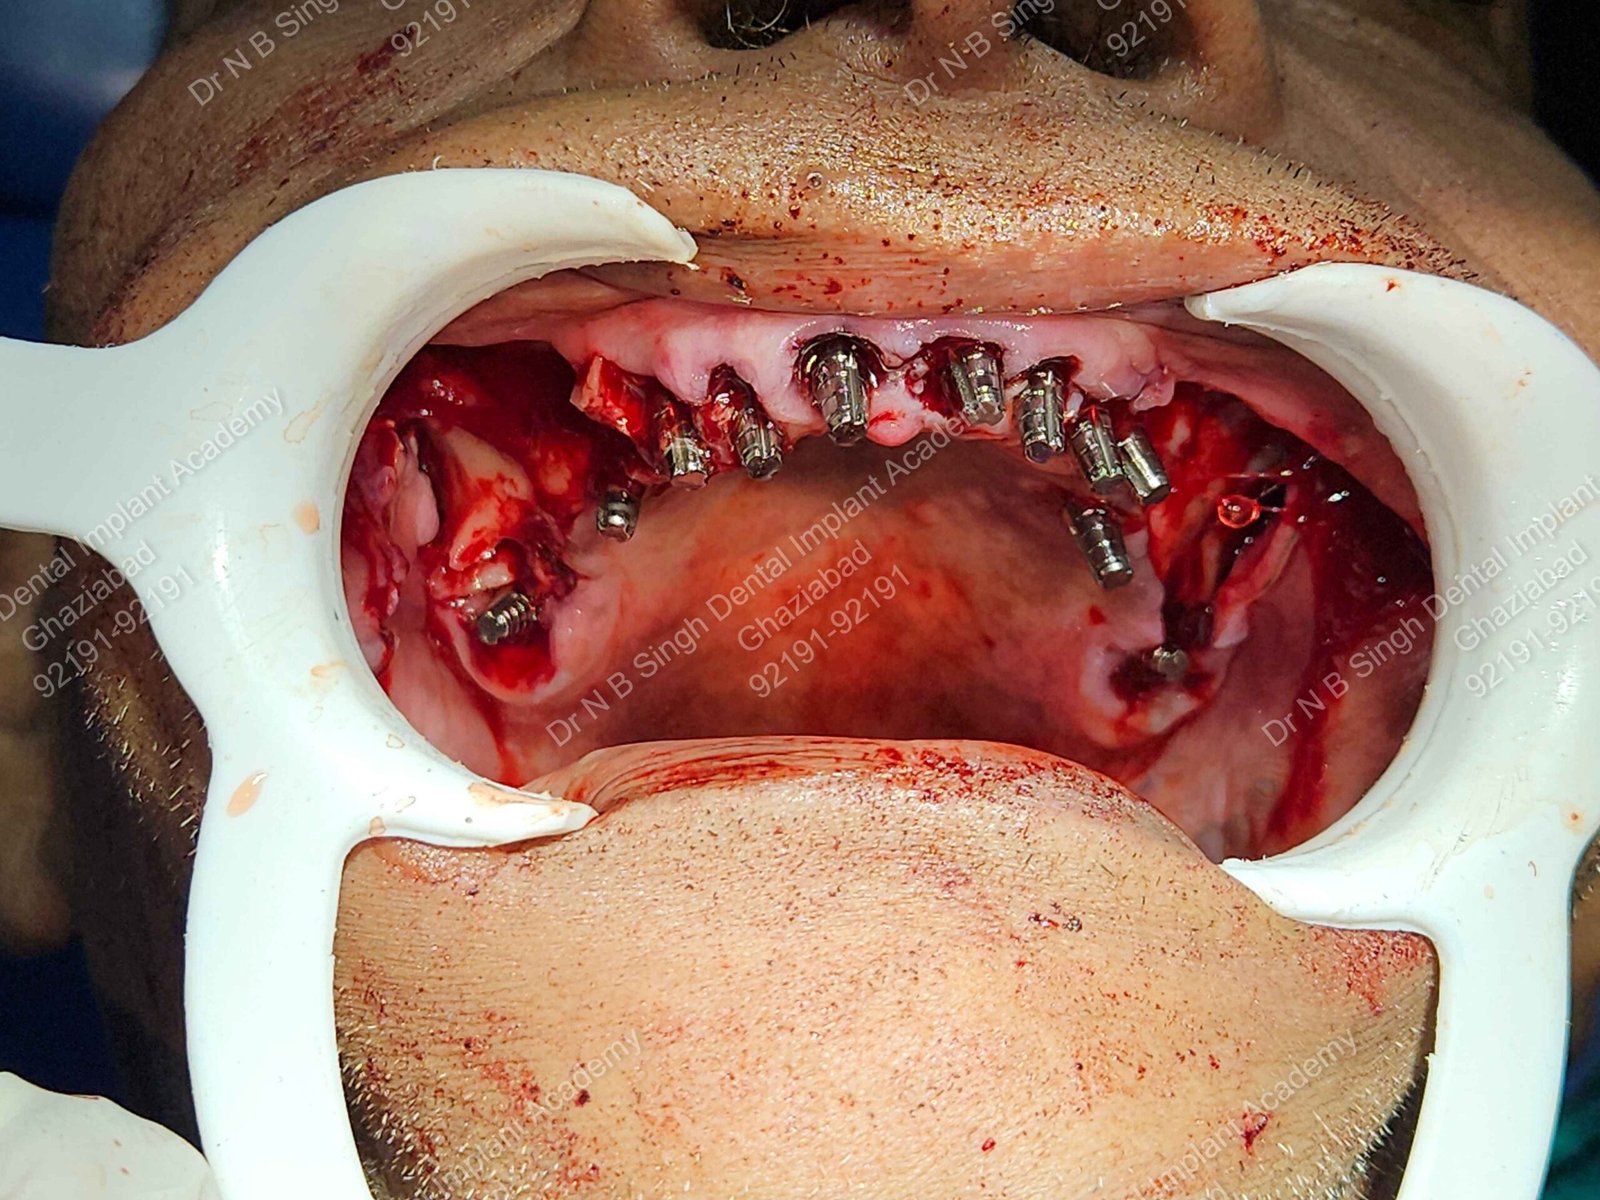

C1005 zygomatic basal implant full mouth – Ali Hasan 4

Dr. N.B. Singh